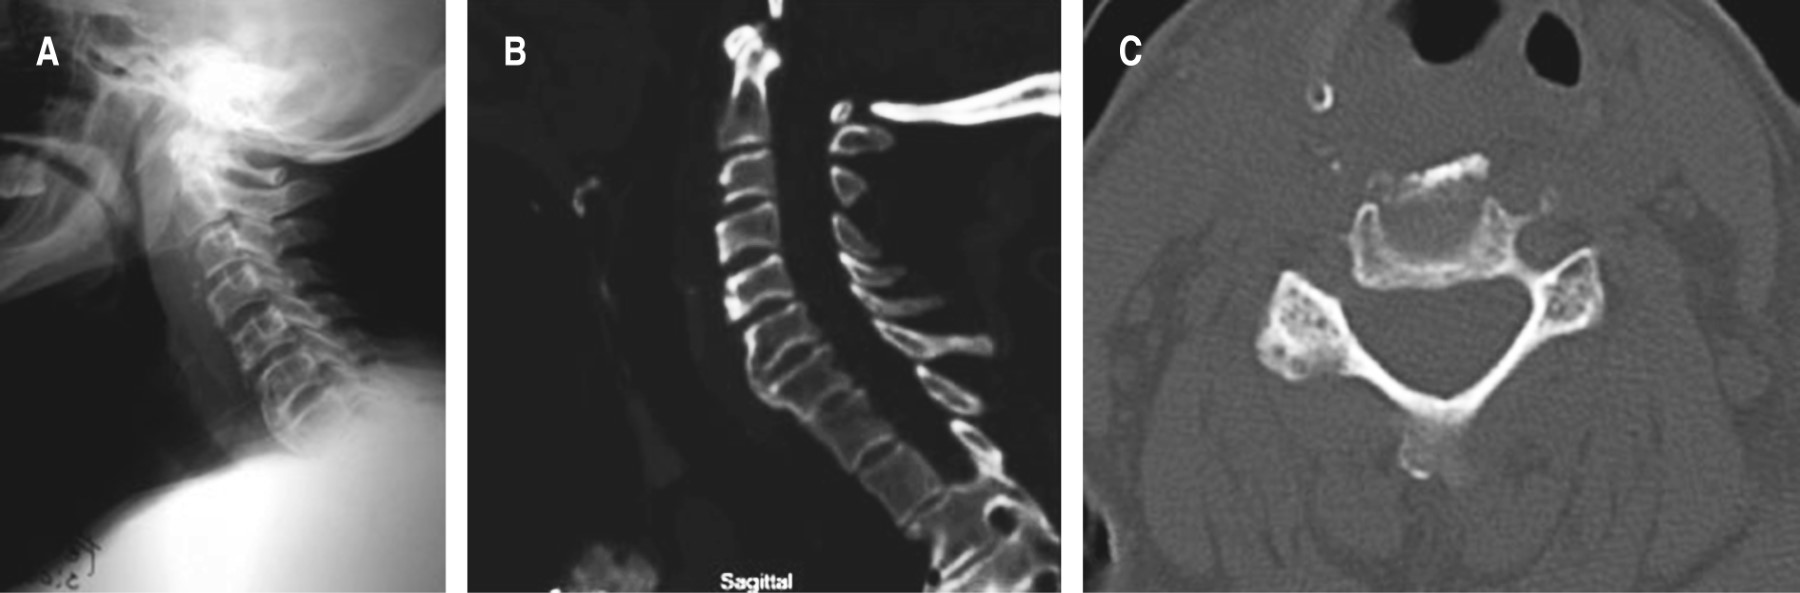

La paciente mostró mejoría sintomática inmediatamente luego de la cirugía. A las dos semanas se retiró el collar cervical, y se le permitió a la paciente ingerir alimentos sin la presencia de signos de disfagia; 10 meses después se realizaron nuevas imágenes sin la presencia de recidivas (Figura 3).

Figura 3